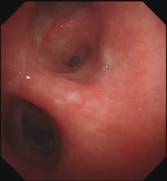

当最后一块异物被取出,患者的气管终于露出了原来的“庐山真面目”:

那堆长达18厘米的痰痂、血痂和痰栓不仅是这次急救成功的有力证明,也让人深感气道管理的重要性。